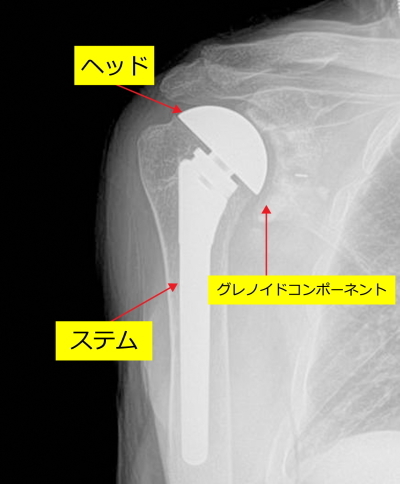

人工関節置換術は以下のイラストのような器具を、肩の肩甲骨と上腕骨に挿入します。イラストをみてください。変形した上腕骨に金属のボール(ヘッド)と芯棒(ステム)を上腕骨に、肩甲骨の関節窩というところにプラスチックの受け皿(イラスト右、グレノイドコンポーネント)を設置します。プラスチックの受け皿は一般的には骨セメントという接着剤で固定します。

下の図はその人工関節が上腕骨と肩甲骨にはいった状態を示しています。ステムとヘッドは連結しています。

人工関節が上腕骨と肩甲骨にはいった状態

下の図はプラスチックの受け皿(プラスチックコンポーネント、医師はグレノイドコンポーネントと呼んでいます)が肩甲骨関節窩に挿入された状態を示しています。

受け皿が肩甲骨関節窩に挿入された状態